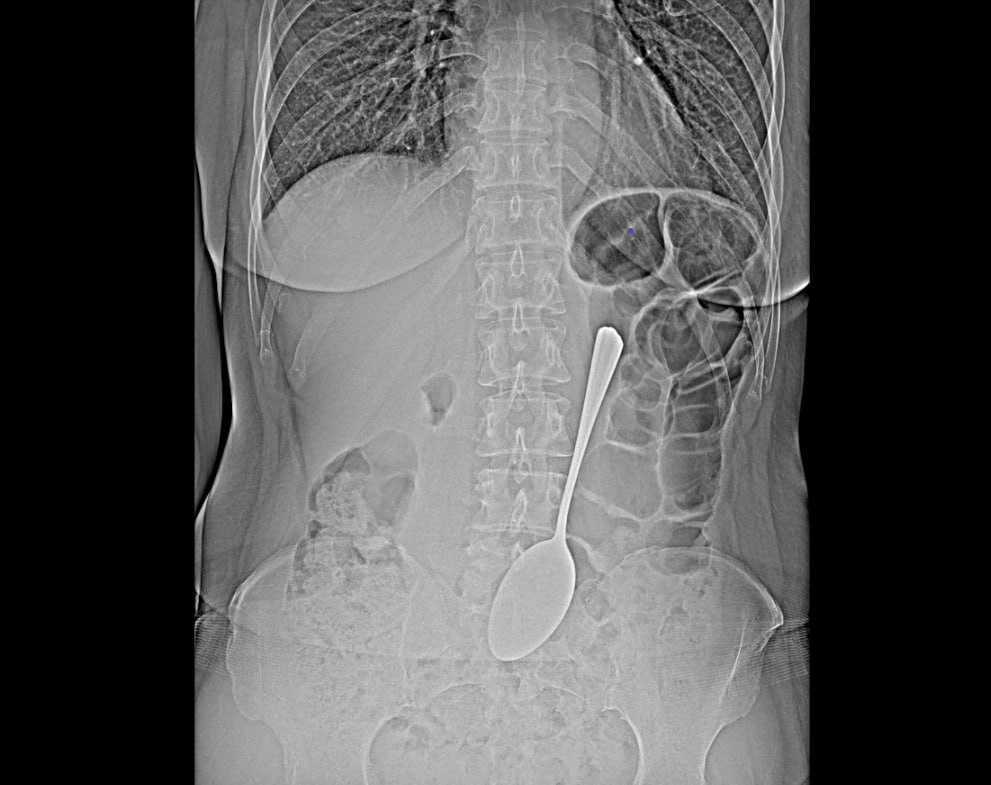

Жительница Бурятии проглотила… ложку длиной 18 см.

Ложку врачи-эндоскописты БСМП сумели достать из желудка с помощью эндоскопа и соответствующих инструментов. Так что женщина избежала сложной хирургической операции